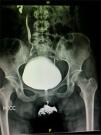

Se hospitalizó para manejo médico con antibiótico, antiespasmódico, anticolinérgico y para realizar urotomografía, el cual demostró ureterocele gigante derecho sin alteraciones anatómicas anexas a esta enfermedad. La paciente evolucionó satisfactoriamente, por lo que fue egresada con su sonda Foley, y 8 días después se realizó cistoscopia encontrando destechamiento isquémico de la pared anterior del ureterocele derecho (fig. 2), uréter contralateral normal (fig. 3) y reflujo vesicoureteral grado IV derecho que fue corroborado por cistograma miccional (figs. 4 y 5), se le realizó reimplante ureteral derecho tipo Cohen, con colocación de catéter doble-J ipsilateral, y un mes después se retiró dicho catéter. La paciente a los 3 meses se encontraba asintomática, y el cultivo y examen general de orina eran normales.

El destechamiento isquémico secundario al tiempo de evolución que presentó nuestra paciente condicionó como complicación reflujo vesicoureteral grado IV, el cual no afectó de forma permanente la función renal, ya que el tratamiento quirúrgico (reimplante ureteral derecho) se realizó adecuadamente.